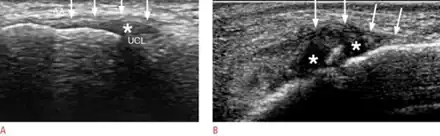

Ultrasound showing a) normal thumb b) gamekeeper’s thumb

Gamekeeper's thumb and skier's thumb are two similar conditions, both of which involve insufficiency of the ulnar collateral ligament (UCL) of the thumb. The chief difference between these two conditions is that skier's thumb is generally considered to be an acute condition acquired after a fall or similar abduction injury to the metacarpophalangeal (MCP) joint of the thumb, whereas gamekeeper's thumb typically refers to a chronic condition which has developed as a result of repeated episodes of lower-grade hyperabduction over a period of time.[7] There are four types of Skier's thumb injury:[7]